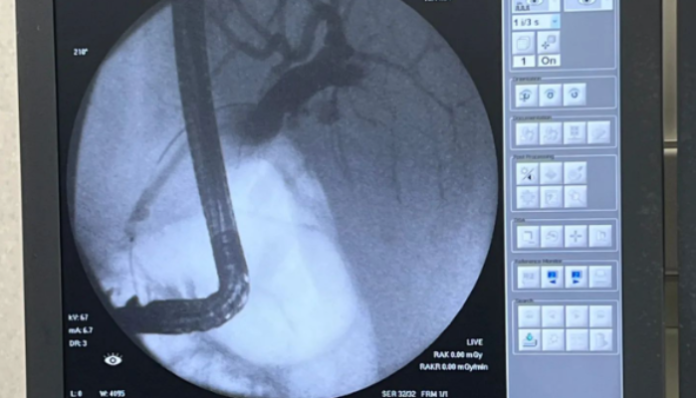

El Hospital de Minas ha alcanzado un hito significativo en el campo de la medicina con la exitosa realización de una colangiopancreatografía retrógrada endoscópica (CPRE). Este procedimiento innovador, que combina la endoscopia gastrointestinal de la parte superior del aparato digestivo y las radiografías, se utiliza para tratar problemas relacionados con los conductos biliares y pancreáticos.

La Dra. Irisarri, reconocida especialista en gastroenterología, lideró este logro junto con el equipo del Block Quirúrgico del Hospital. Su experiencia y dedicación han sido fundamentales para llevar a cabo este procedimiento pionero en el centro de salud. La CPRE es una técnica compleja que requiere habilidades especializadas y una meticulosa coordinación entre los profesionales médicos y radiólogos.

La CPRE se utiliza para diagnosticar y tratar afecciones como cálculos biliares, estenosis de los conductos biliares, tumores y pancreatitis. Al combinar la endoscopia con las radiografías, los médicos pueden visualizar con precisión los conductos biliares y pancreáticos, y realizar intervenciones terapéuticas cuando sea necesario.